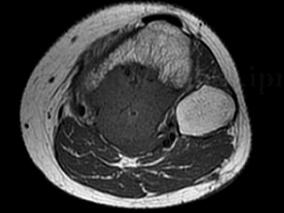

1小时条评论49岁女性,右大腿软组织肿物手术后反复发作4年半。软组织肉瘤的诊断需要临床、影像学、病理相结合。对于临床表现、影像学表现与病理结果不相符的病例,特别需要注意。如何进行明确诊断? (1)病例摘要 :患者,女性,49岁,因右大腿软组织肿物手术后反复发作4年半...